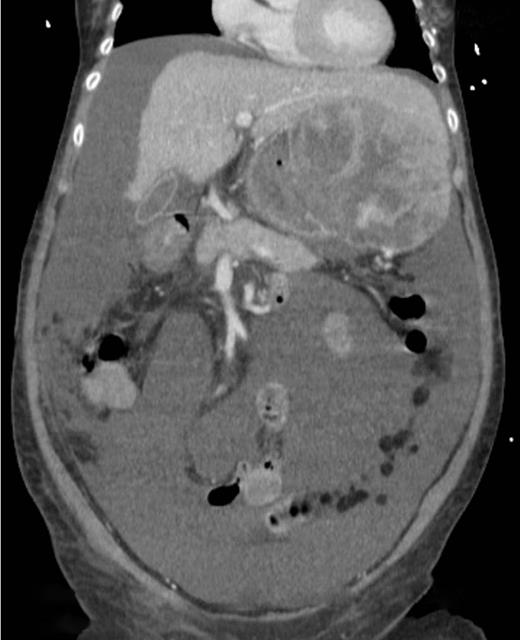

A computed tomography scan was performed which showed multifocal HCC with a large exophytic lesion invading into the greater curvature of the stomach (Figs. 3 and 4). Peritoneal metastases and ascites were present. The patient underwent an angioembolization of the hepatic tumour on the same evening. Angiography identified a replaced left hepatic artery as the dominant vessel supplying the lesion of concern in the left lateral hepatic segment (Fig. 5a). Gelfoam embolization was performed with no residual tumour enhancement thereafter (Fig. 5b).

Computed tomography image showing tumour originating from the liver.